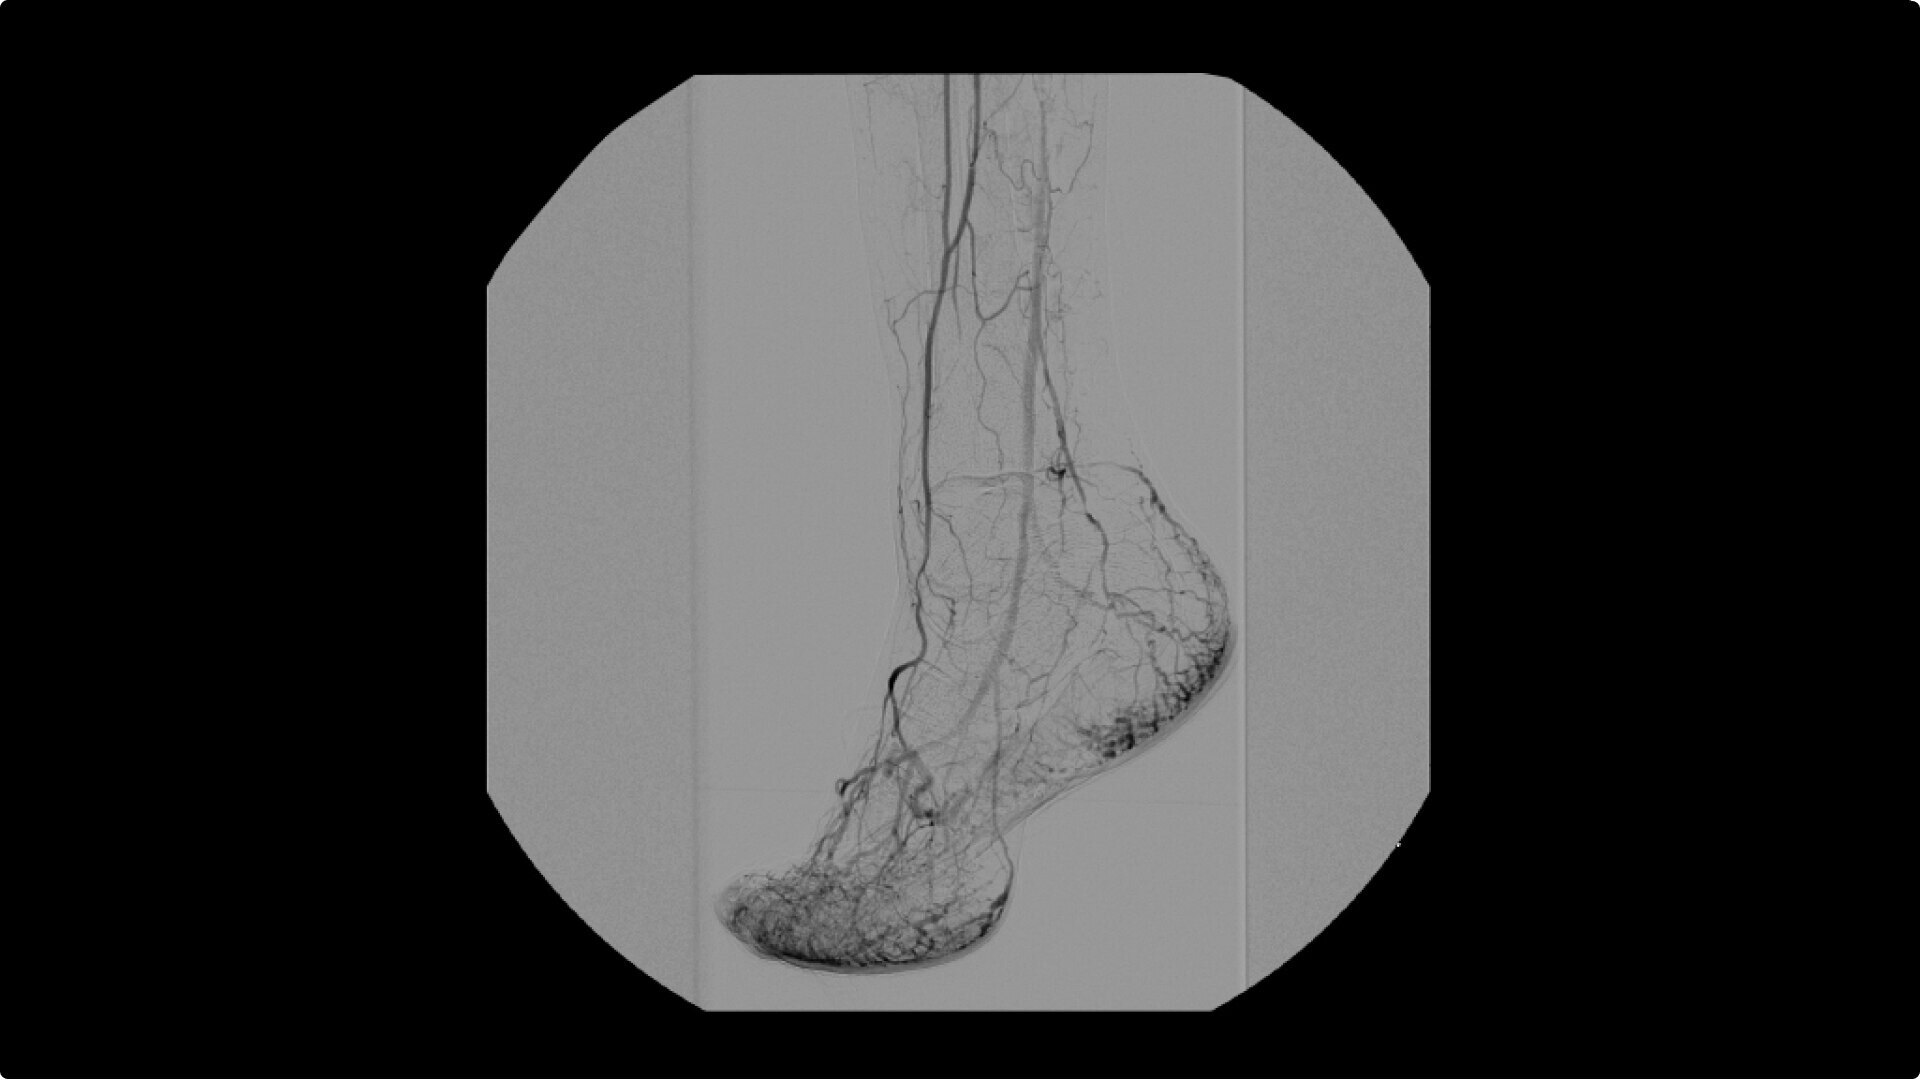

OEC C-arms are used by interventionalists and surgeons to obtain vascular imaging during peripheral to contrast run-off procedures. Superb resolution, even in the presence of motion, enables easy identification of anatomical landmarks and the extremity of the catheter, even as catheter tip moves.

Perform a full leg Bolus Chase in one contrast run with a Preset Profile that includes Motion Tolerant Subtraction, that dynamically adjusts image quality based on presence of motion.

During contrast run-off procedures, easily select contrast type with positive (e.g. Iodine) or negative (e.g. Carbon Dioxide) during subtraction. The OEC Elite CFD cardiovascular package also includes Roadmapping.